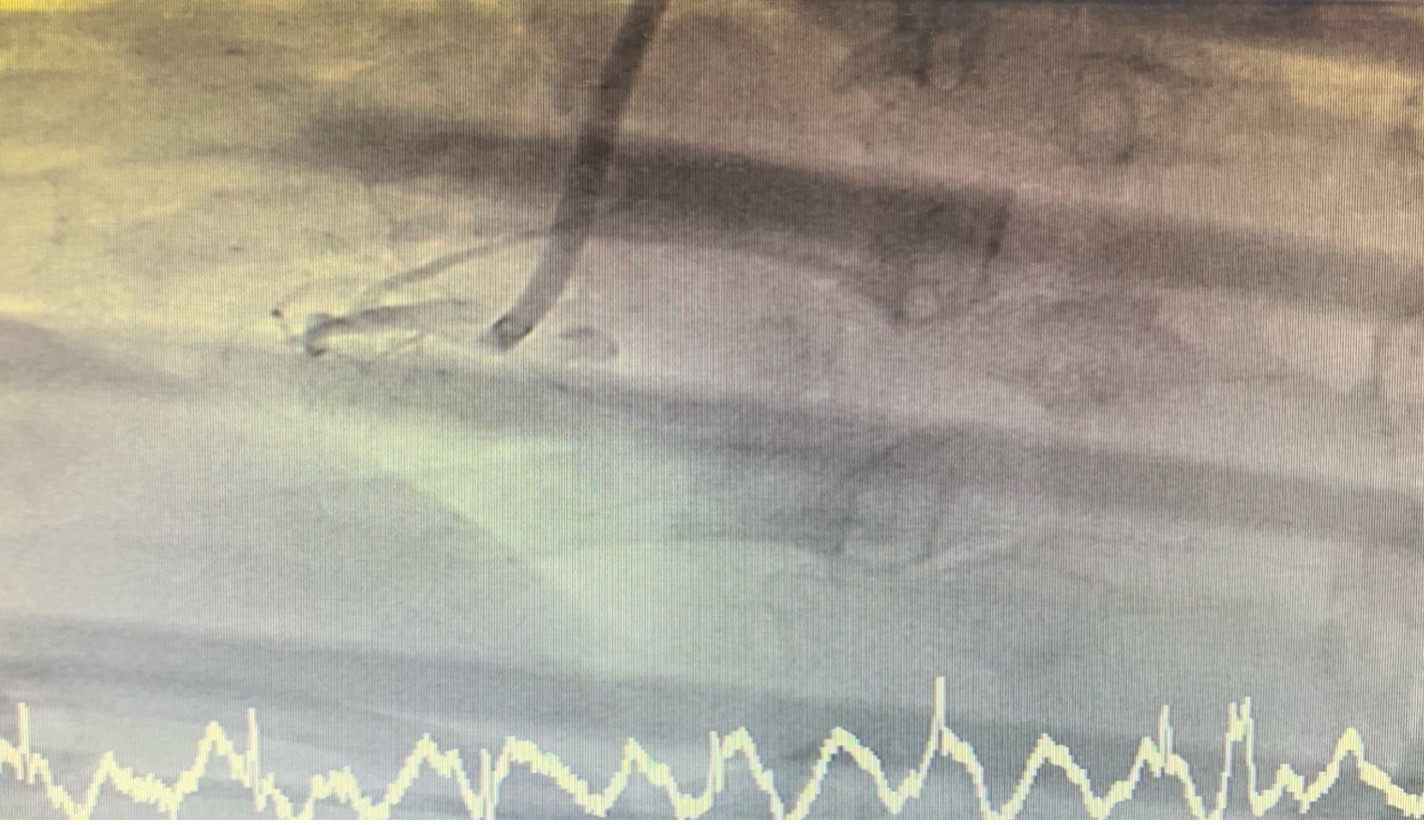

Coronary angiogram (CAG) via right femoral approach with JL 6/4 diagnostic catheter, JR 6/4 guiding catheter catheter showed normal Left main (LM), mild irregular, non significant stenosis left anterior descending artery LAD, LCx, complete blockage of proximal RCA.

CAG showed normal Left main, mild irregular, non significant stenosis left anterior descending artery, LCx , complete blockage of proximal RCA.

PCI with JR 6/4 guiding catheter and wiring with Turntrac to RCA. Predilated with 2.0 x 15 mm Semi-compliant balloon upto 14 atm. Biolimus eluting stent deployed proximal RCA upto 10 atm, Balloon stent post dilated upto 14 atm. The final angiogram was acceptable result. Inserted temporary pacemaker via right femoral vein. After arrived CCU the patient developed cardiac arrest c VT storm. Left Stellate ganglion block was done during CPR and successful suppression of VT storm .